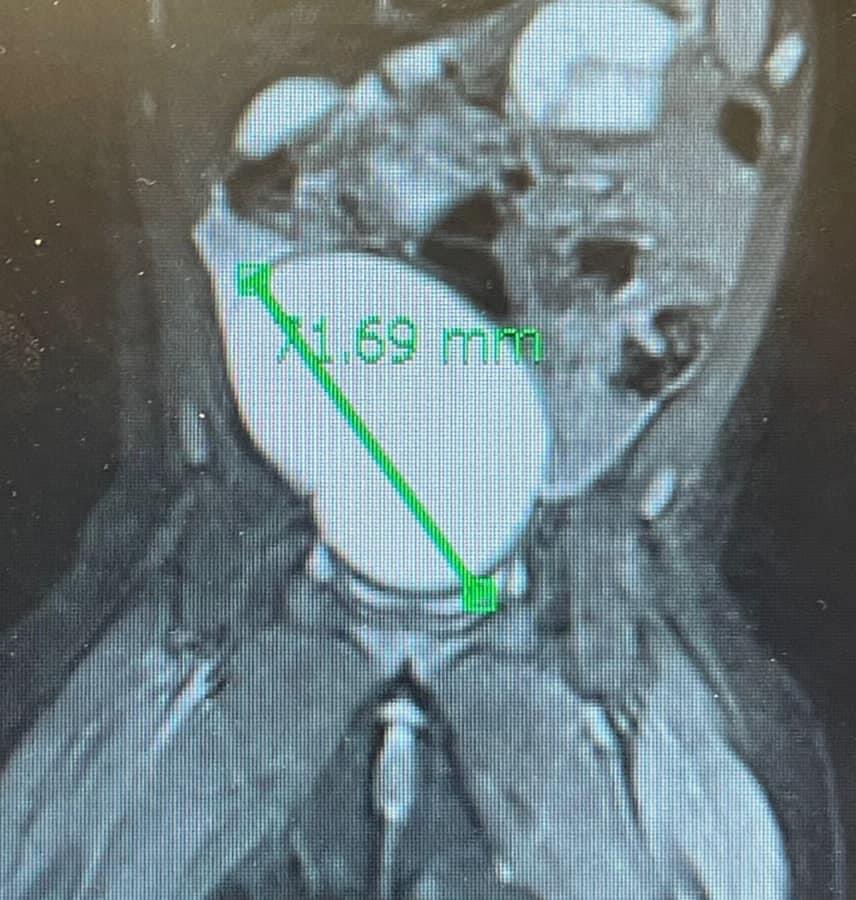

Durmadan ağlayan və qusan 3 aylıq qız uşağı üçün valideynləri tərəfindən Mərkəzi Klinikaya müraciət olunub. Müayinələr zamanı uşağın yumurtalığında qarın boşluğu və çanağı tutan nəhəng ölçülü kistanın mövcud olduğu orta çıxıb.

Uzman həkim bildirib ki, nəhəng ölçülü kistaya bağlı yumurtalığın burulma, yəni itirilmə təhlükəsi olduğu üçün körpə məcburi əməliyyata alınıb. Əməliyyat qapalı yolla laparoskopik olaraq həyata keçirilib:

"Cərrahi əməliyyat zamanı kistanın içərisindən təqribən 150 ml maye boşaldılıb. Körpə qızın yumurtalığı qorunaraq kista çıxarılıb.

Əməliyyat uğurlu keçib".